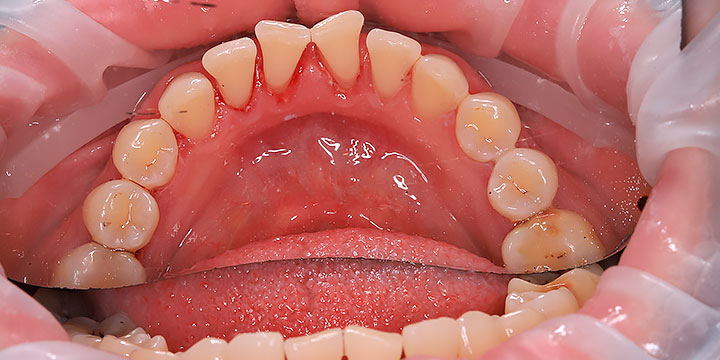

В Дева-Дент я работаю стоматологом-гигиенистом с уклоном в хирургию и пародонтологию. При гигиене я особенно обращаю внимание на состояние дёсен и работаю по протоколу пародонтологической настороженности.

Качественная гигиена — это мой конёк!

Прекрасно понимаю, что визит к стоматологу может вызывать тревогу. Поэтому я делаю все возможное, чтобы создать максимально комфортную и спокойную атмосферу, подробно объясняю каждый этап процедуры и всегда открыт для ваших вопросов. Моя миссия проста: сохранить ваши зубы здоровыми и красивыми на долгие годы с помощью эффективной профилактики.